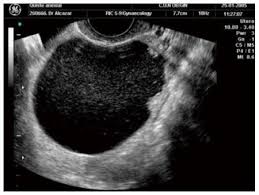

Ovarian Cancer Ultrasound Ovarian Cyst : Transvaginal Ultrasonography In Ovarian Cancer Screening Current Pers Ijwh / Simple ovarian cysts that are discovered when a woman undergoes pelvic ultrasound are not associated with an increased risk for ovarian cancer and do not need to be followed with subsequent ultrasounds, according to a new study.. Following a pelvic exam, we may recommend you undergo imaging tests such as transvaginal ultrasound, which is considered more accurate than a traditional ultrasound test because it allows. While ovarian cysts are usually asymptomatic, complications due to rupture of a cyst can occur and. Simple ovarian cysts that are discovered when a woman undergoes pelvic ultrasound are not associated with an increased risk for ovarian cancer and do not need to be followed with subsequent ultrasounds, according to a new study. Your specialist may ask you to have a ct scan to show the ovaries more clearly. 1— classic ap pearances of f unctional cysts.

Transvaginal ultrasound (tvuss) is very useful in detecting ovarian cysts and assessing their malignant potential, but requires specialist sonographers and would be expensive to. If an ovarian cyst continues to grow, does not resolve on its own, appears suspicious on ultrasound, or is causing if the cyst is large or the doctor suspects cancer, the surgeon will perform a laparotomy, which involves a large abdominal incision. Most ovarian cysts are small, harmless, and resolve without treatment. Callen's ultrasonography in obstetrics and gynecology. Ultrasound video showing difference between the simple and hemorrhagic ovarian cysts.

Things that may make you more likely to get ovarian cysts include american family physician: Regular ultrasound scans and blood tests are usually recommended over the course of a year to monitor the cyst. Ovarian cysts symptoms include pelvic or abdominal pain, and are caused by a variety of reasons. Algorithm based on a systematic review recurrence of ovarian endometrioma in adolescents after conservative, laparoscopic cyst enucleation ovarian cancer including fallopian tube cancer & primary peritoneal cancer., vol. Vaginal ultrasound can help to show whether any cysts on your ovaries contain cancer or not. Ovarian cysts occur commonly in women of all ages. Most ovarian cysts are benign (not cancer) and go away on their own without treatment. Authored by elisa ross, md and chelsea fortin, md of the for the vast majority of women, ovarian cysts are not precancerous lesions and do not increase the risk of developing ovarian cancer later in life.